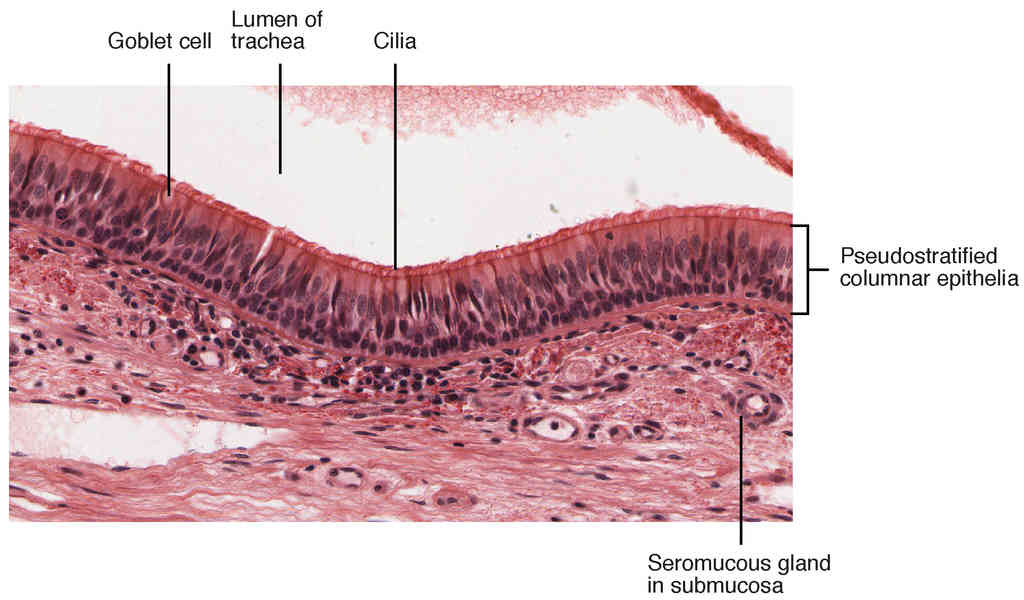

This page is under construction. For now, it is just a resource of the images found in the OpenStax Anatomy and Physiology Handbook. It wil slowly change into a revision tool. Each slide has a number. Use this to refer to the slide. When completed, it will have an unlabelled section, with labelled slides in parallel. On the unlabelled slides, write your answer and use the labelled slide to assess yourself. Keep track by also noting the number on each slide. Improvement at each attempt is important, more so than full marks on a first attempt.